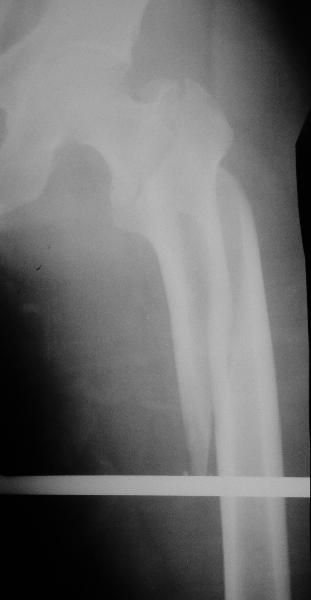

Дорогие коллеги, Как правильно определить такой перелом по классификации AO?

Как два отдельных или есть один соответствующий код? Фиксировать-то оба можно одним фиксатором...